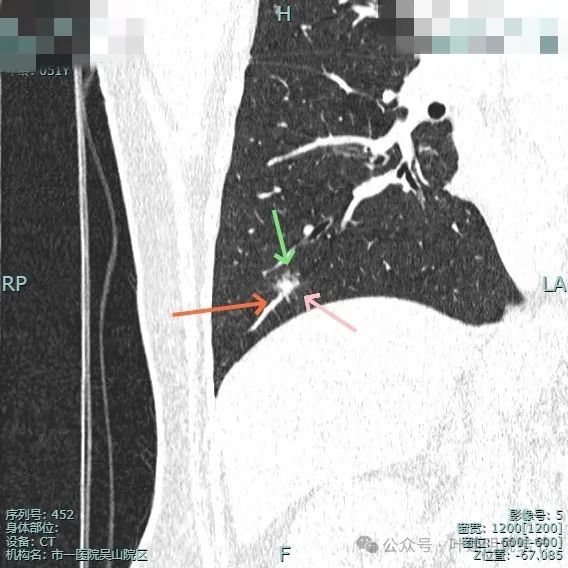

再看在我门诊时2025年1月14号复查的靶扫描影像:

明显的血管进入与异常增粗。

灶内密度杂乱,血管进入与增粗,表面不平。

血管进入与异常增粗并散开来(在肿瘤性病变中,这种表现是浸润性而且风险大的表现)。

血管进入穿行并异常增粗,磨玻璃成分显得较为散在,缺乏聚拢性。